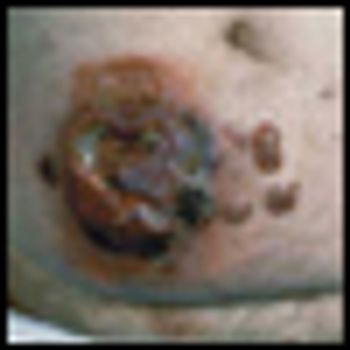

Mycosis fungoides (MF), the most common cutaneous T-cell lymphoma, is a low-grade cutaneous lymphoma characterized by skin-homing CD4+ T cells. It is notable for highly symptomatic progressive skin lesions, including patches, plaques, tumors, and erytheroderma, and has a poorer prognosis at later stages. Diagnosis remains difficult owing to MF’s nonspecific skin presentation and identification of the optimal treatment strategy is challenging given the paucity of controlled trials and numerous and emerging treatment options. Management includes topical therapy with the addition of systemic therapy for patients with later-stage disease including tumors; erythroderma; and nodal, visceral, or blood involvement. Topical therapies include mechlorethamine (nitrogen mustard), carmustine (BCNU), steroids, bexarotene gel (Targretin Gel), psoralen plus ultraviolet A (PUVA), ultraviolet B (UVB), and either localized or total skin electron radiotherapy. Systemic therapies include interferon, retinoids, oral bexarotene (Targretin), denileukin diftitox (Ontak), vorinostat (Zolinza), extracorporeal photochemotherapy (photopheresis), and cytotoxic chemotherapy. Herein, we outline clinically relevant aspects of MF, including clinical presentation, pathology, diagnosis, and staging. We describe in detail existing and emerging therapeutics and offer specific recommendations for management of each stage of MF.